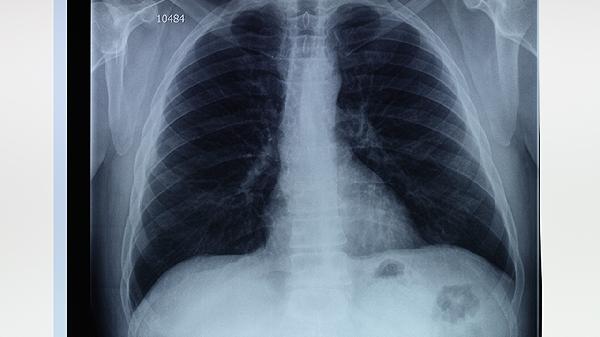

肺大泡患者应保持居住环境空气清新,避免剧烈运动和潜水等可能引发气胸的活动。饮食需保证优质蛋白摄入,如鱼肉、蛋清等,适量补充维生素C增强抵抗力。建议每3-6个月复查胸部CT,监测肺大泡变化情况,出现突发胸痛或呼吸困难需立即就医。